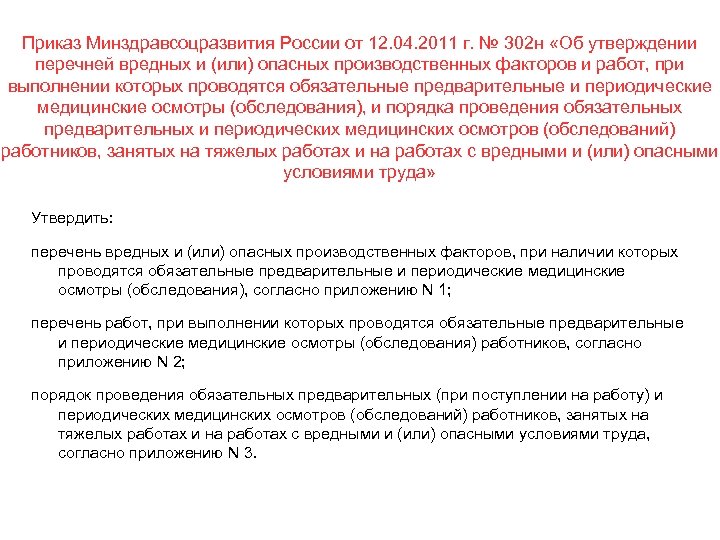

Приказ Минздравсоцразвития России от 12. 04. 2011 г. № 302 н «Об утверждении перечней вредных и (или) опасных производственных факторов и работ, при выполнении которых проводятся обязательные предварительные и периодические медицинские осмотры (обследования), и порядка проведения обязательных предварительных и периодических медицинских осмотров (обследований) работников, занятых на тяжелых работах и на работах с вредными и (или) опасными условиями труда» Утвердить: перечень вредных и (или) опасных производственных факторов, при наличии которых проводятся обязательные предварительные и периодические медицинские осмотры (обследования), согласно приложению N 1; перечень работ, при выполнении которых проводятся обязательные предварительные и периодические медицинские осмотры (обследования) работников, согласно приложению N 2; порядок проведения обязательных предварительных (при поступлении на работу) и периодических медицинских осмотров (обследований) работников, занятых на тяжелых работах и на работах с вредными и (или) опасными условиями труда, согласно приложению N 3.

Приказ Минздравсоцразвития России от 12. 04. 2011 г. № 302 н «Об утверждении перечней вредных и (или) опасных производственных факторов и работ, при выполнении которых проводятся обязательные предварительные и периодические медицинские осмотры (обследования), и порядка проведения обязательных предварительных и периодических медицинских осмотров (обследований) работников, занятых на тяжелых работах и на работах с вредными и (или) опасными условиями труда» Утвердить: перечень вредных и (или) опасных производственных факторов, при наличии которых проводятся обязательные предварительные и периодические медицинские осмотры (обследования), согласно приложению N 1; перечень работ, при выполнении которых проводятся обязательные предварительные и периодические медицинские осмотры (обследования) работников, согласно приложению N 2; порядок проведения обязательных предварительных (при поступлении на работу) и периодических медицинских осмотров (обследований) работников, занятых на тяжелых работах и на работах с вредными и (или) опасными условиями труда, согласно приложению N 3.